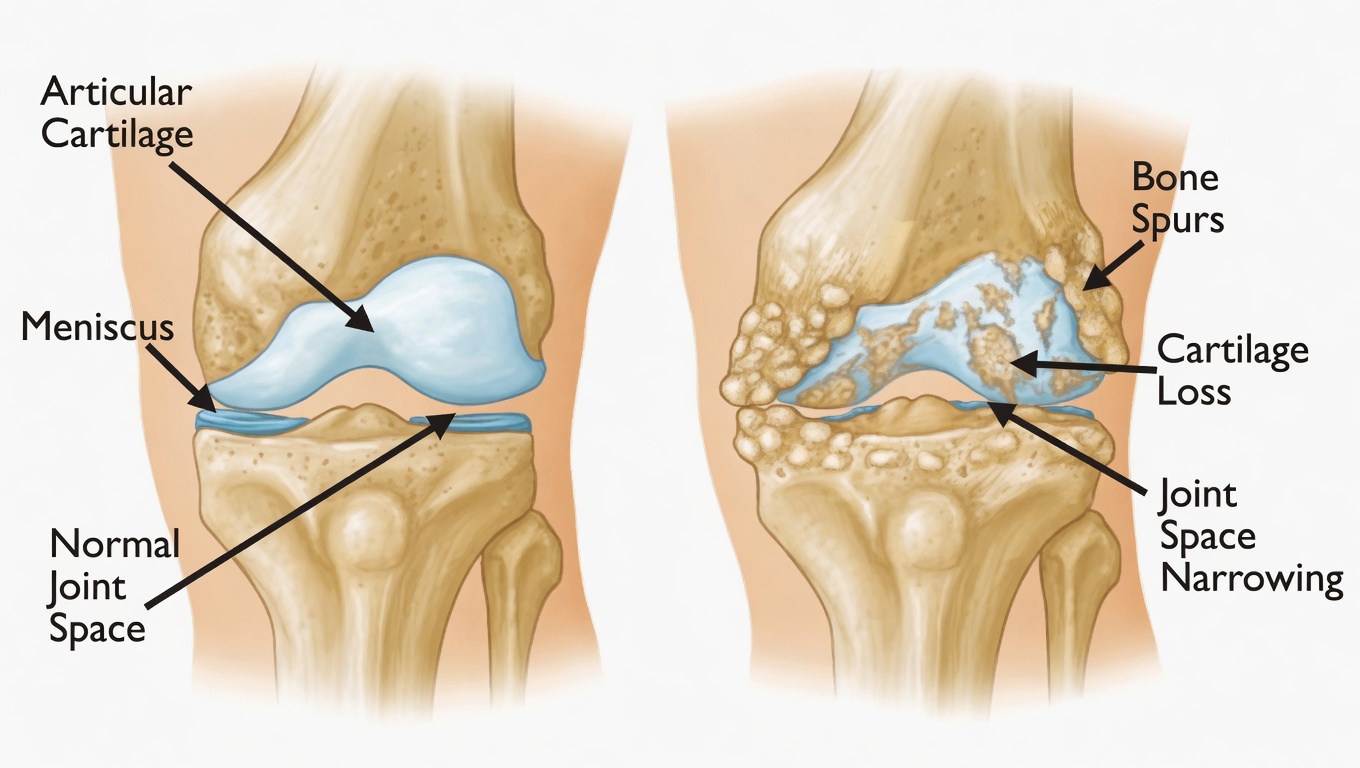

Persistent inflammation inside the joints can cause swelling and tenderness that make simple movements, like buttoning a shirt or holding a coffee mug, feel nearly impossible. Over time, this can create a constant sense of limitation and discouragement.

- If left unmanaged, rheumatoid arthritis can accelerate joint destruction and severe fatigue, further eroding quality of life.